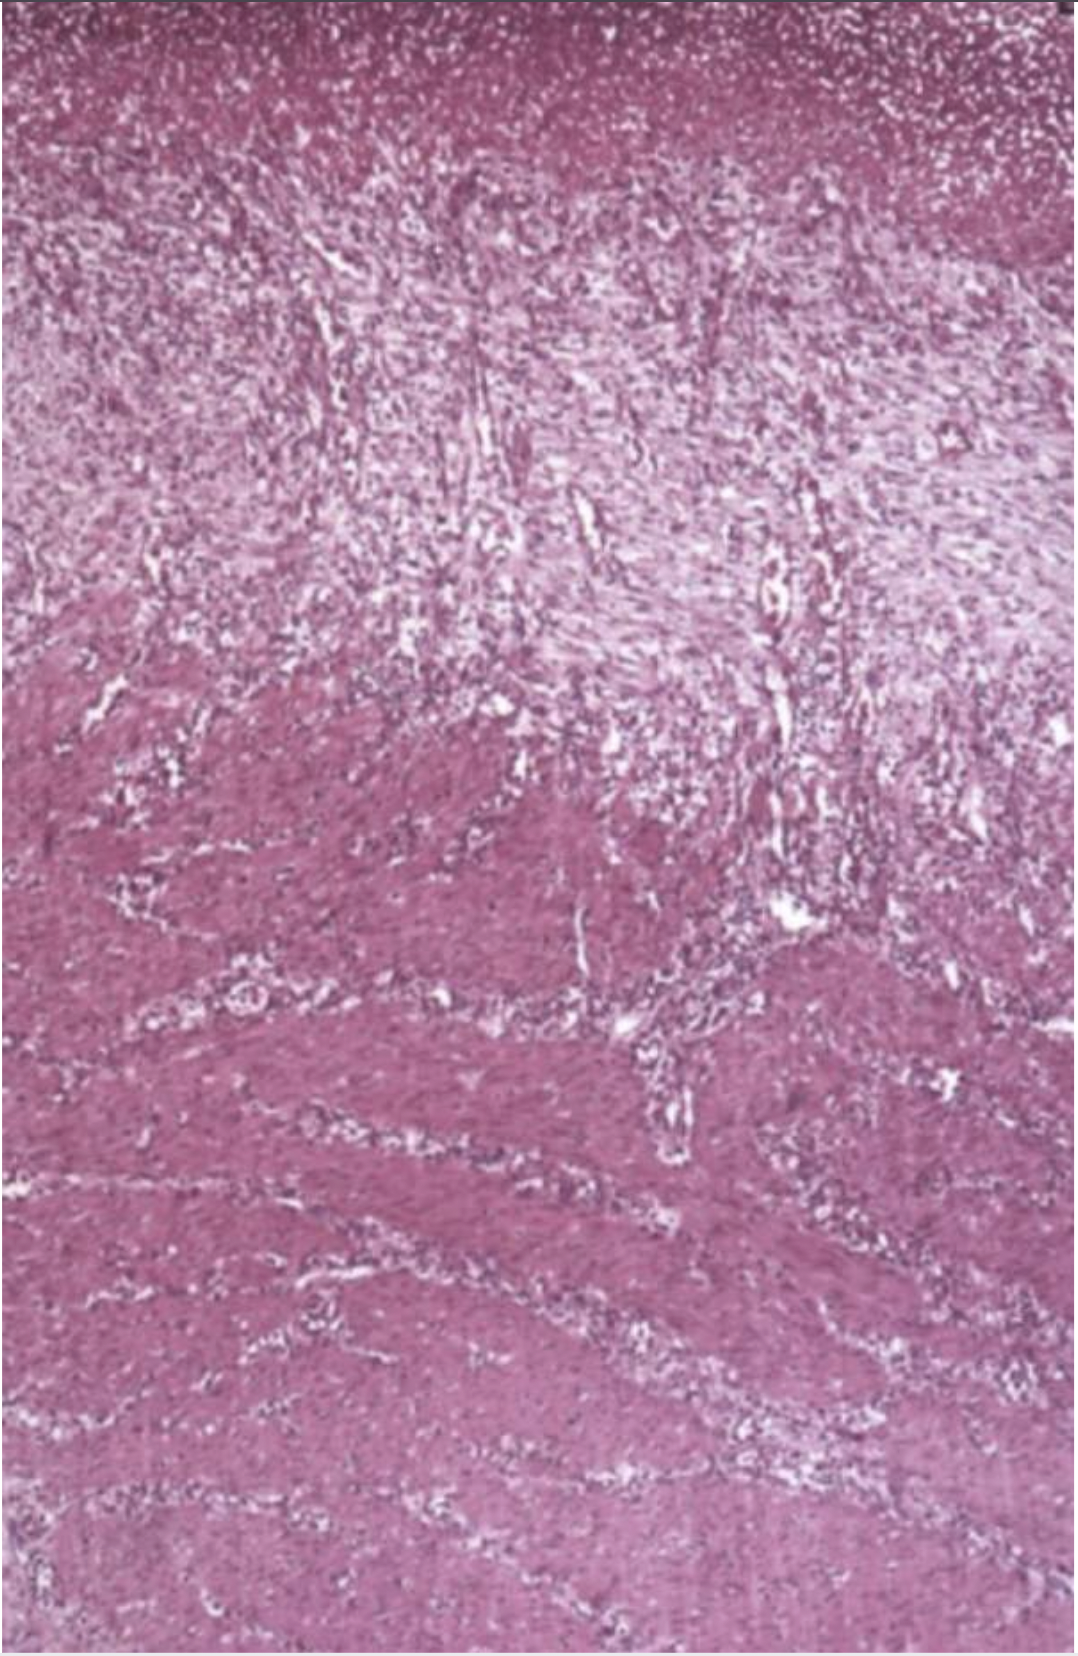

What can you see in this image?

Scar tissue- pale and pinkish

Bottom part: muscle with canals of lymphocytes and slits in the faded part are blood vessels